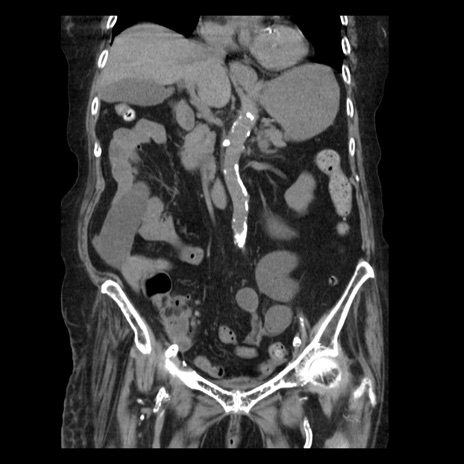

症例14(冠状断像)

【症例】 90歳代女性

【主訴】 腹痛・嘔吐

【現病歴】今朝から左側腹部痛を認めた。 経過観察していたが、嘔吐を認めたため来院。

【既往歴】 子宮癌術後

【身体所見】 意識清明、BP 127/54mmHg、P 98bpm Sp02 95%(RA)、BT 35.8°C、腹部平坦・軟腸ぜん動音聴取良好、右下腹部圧痛(+) 反跳痛なし

【データ】WBC 9800、CRP 0.46